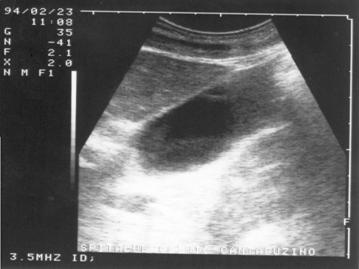

Imaginea transsonica

Structurile lichidiene (sangele, bila, secretiile digestive, continutul chistelor, ascita, colectia pleurala) sunt strabatute de catre ultrasunete in totalitate, fara a exista nici un fel de reflexii pe traseul acestora. Imaginea ecografica, fiind expresia unei "lipse de ecouri", va avea aspectul opus structurilor ecogene, respectiv culoarea neagra. O structura lichidiana este definita in ecografie prin termenul de transsonic.

Exemple:

structuri transsonice normale: colecist, vezica urinara, lumen vascular;

structuri transsonice patologice: chistul, continutul necrozat al unui abces sau al unei tumori maligne.

Figura 1. Vezica urinara

Figura 2. Chist renal stang situat in treimea medie

Figura 3. Chist ovar drept

Figura 4. Chist hepatic